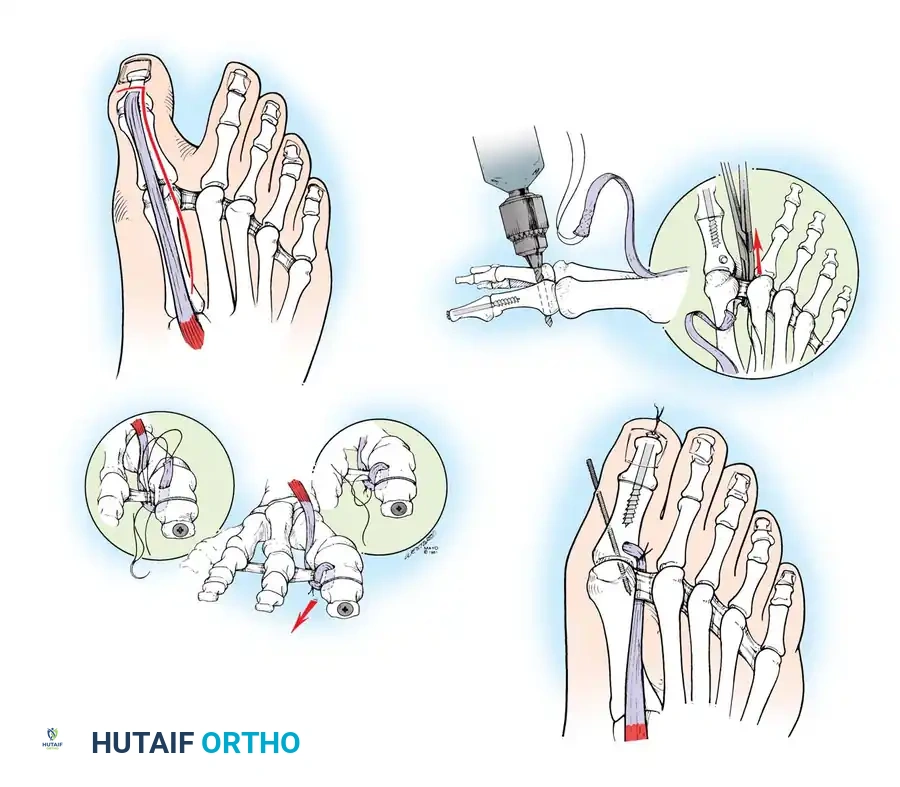

Modifi ed McBride Bunionectomy TECHNIQUE 78-1

SKIN AND CAPSULAR INCISION

• With the patient supine and a tourniquet on the limb, extend a midline, straight, medial incision from the middle of the proximal phalanx to 2 cm proximal to the junction of the medial eminence with the metatarsal shaft (Fig. 78-13). This incision usually is in an internervous plane between the most medial branches of the superfi cial peroneal nerve dorsally and the medial proper digital branch of the medial plantar nerve plantarward. (McBride recommended a single incision beginning at the fi rst web space and extending proximally and medially across the metatarsal, ending on the medial side of the fi rst metatarsal proximal to the exostosis.)

• Mobilize the skin 2 to 3 mm dorsally and plantarward to ensure that no sensory nerve would be injured by the capsular incision.

• Coagulate the superfi cial veins as encountered to minimize postoperative bleeding.

• Use delicate, two-tooth retractors and 1.5-mm forceps in this initial dissection to avoid unnecessary skin trauma.

• Make a longitudinal capsular incision (the original McBride capsular incision was transverse) 3 to 4 mm plantar to the line of the skin incision (Fig. 78-14).

Modifi ed McBride Bunionectomy TECHNIQUE 78-1—cont’d

• By sharp dissection, raise the periosteum and the capsule dorsally and plantarward from the base of the proximal phalanx to the proximal edge of the medial eminence (Fig. 78-15). At the proximal end of the medial eminence, avoid releasing the proximal bony attachments of the medial capsule on the metatarsal neck (especially in the dorsal direction) in an attempt to expose the medial eminence. To ensure adequate exposure without disruption of this proximal attachment, a longitudinal capsular incision is suggested.

• Elevate the capsule by sharp dissection dorsalward and plantarward to expose the dorsal aspect of the metatarsal head, the entire medial eminence, and the plantar plate. A periosteal elevator is not recommended because of the possibility that the proximal attachments of the capsule may be released.

L-SHAPED CAPSULAR INCISION

• Alternatively, make the capsular incision in an inverted L shape (Fig. 78-16A).

• Raise the dorsal fl ap deep to the nerve and veins until the accessory slip of the extensor hallucis longus tendon is seen in the proximal portion of the incision where it is easier to identify. The tendon almost always can be located with careful searching. If it is not seen at the dorsomedial aspect of the fi rst metatarsal, however, begin the longitudinal limb of the incision at this slope of the metatarsal from dorsal to medial.

• Begin the incision proximally on the dorsomedial side of the fi rst metatarsal shaft and 2 to 3 mm medial to the accessory slip of the extensor hallucis longus tendon. Carry the incision to the bone at the level of the fi rst metatarsal joint, extending proximally 4 to 6 cm.

• Make the transverse limb of the capsular incision at the level of the joint, stopping 2 to 3 mm from the tibial sesamoid bone; this limb transects the capsular insertion of the abductor hallucis muscle (Fig. 78-16B and C).

• Beginning on the plantar aspect of the incision, remove the capsule from the medial eminence from the inside out. Avoid buttonholing the capsule at the junction of the medial eminence and the metatarsal by directing the small-bladed knife down the slope of the eminence.

• Free the capsule subperiosteally on its dorsomedial surface, and retract it proximally and plantarward (Fig. 78-16D).

• Insert one small Hohmann retractor over the dorsolateral surface of the metatarsal head and another beneath the head at the head and neck junction, while distracting and plantar fl exing the hallux to expose the articular surface of the metatarsal head for evaluation of its condition and orientation. Reduce the hallux congruently on the metatarsal head.

• If the hallux is in more than 15 degrees of valgus after reduction, a distal metatarsal osteotomy is needed.

MEDIAL EMINENCE REMOVAL

• After inspecting the metatarsophalangeal joint for degenerative changes, loose bodies, or synovial abnormalities, remove the medial eminence by fi rst scoring with an osteotome its proximal edge where the eminence meets the shaft. Always consult the preoperative radiographs to determine how much of the medial eminence should be removed.

• Using the same osteotome or a power saw, begin the exostectomy distally at the parasagittal groove, and direct it medially toward the scored area on the metatarsal shaft (Fig. 7817). If a power saw is used, a 9-mm blade, rather than a 4to 5mm blade, is preferred. The medial direction of the osteotomy prevents splitting of the metatarsal shaft, especially if the proximal edge of the osteotomy has been scored as recommended.

• After the medial eminence has been removed, use a small rongeur to round off the dorsal and plantar edges of the medial aspect of the metatarsal head. Rasping the raw bone concludes the initial stage of the procedure. Use bone wax on the raw surfaces of bone of the metatarsal head.

ADDUCTOR TENDON AND LATERAL CAPSULAR RELEASE

• Begin the second stage with a dorsal longitudinal incision beginning 2 to 3 mm proximal to the dorsal aspect of the fi rst web space to avoid web contracture postoperatively; extend it proximally between the fi rst and second metatarsal heads for 3 to 4 cm (Fig. 78-18). This allows adequate exposure of the adductor insertion into the base of the proximal phalanx, the lateral head of the fl exor hallucis brevis muscle converging on the fi bular sesamoid, and the entire lateral capsule from the extensor hallucis longus muscle to the plantar plate.

• The main portion of the adductor tendon inserts into the base of the proximal phalanx just plantar to the longitudinal axis of the phalanx. It also has a smaller insertion, along with the lateral head of the fl exor hallucis brevis muscle, into the fi bular sesamoid. The simplest technique to identify the insertion of the adductor hallucis tendon is to place a small, pointed, curved hemostat on the dorsolateral base of the proximal phalanx, slide it fi rmly plantarward, and lift the hemostat dorsally and laterally; the tip of the instrument usually rests in the axilla of the insertion of the adductor tendon (Fig. 78-19A). This is comparable to securing the iliopsoas tendon for tenotomy at the lesser trochanter.

• When the primary insertion is released, grasp the tendon with forceps or a hemostat, and, with traction, displace it dorsally and laterally toward the second metatarsal so that further dissection is on the medial side of the adductor or push the sesamoid sling laterally through the previously placed medial incision to aid exposure.

• While spreading the fi rst and second metatarsal heads with a small Inge retractor, heavy-duty two-tooth retractors, or a Weitlaner retractor, hold the adductor tendon under tension, which facilitates exposure. The lateral head of the fl exor hallucis brevis muscle, the lateral border of the fi bular sesamoid, and the slip of the adductor tendon (confl uent with the lateral head of the fl exor hallucis brevis muscle) come into view in the depths of the wound.

• All attachments of the adductor into its conjoined insertion with the lateral head of the fl exor hallucis brevis muscle into the fi bular sesamoid must be severed; with traction on the adductor, it freely and independently moves without tethering the fi bular sesamoid (Fig. 78-19B).

• This deep transverse intermetatarsal ligament, which lies just plantar to the adductor, may be released by the incision along the lateral border of the sesamoid. If not, release this ligament, carefully preserving the neurovascular bundle immediately beneath it, and incise the lateral capsule. Mann emphasized that release of the deep transverse metatarsal ligament endangers the neurovascular bundle to the fi rst web space, which lies immediately beneath this ligament. Sliding a small Freer elevator between this ligament and the neurovascular bundle would protect the latter structures.

FIBULAR (LATERAL) SESAMOIDECTOMY: DORSAL APPROACH

• If after complete adductor hallucis release and preferably after a lateral capsular release, a fi bular sesamoidectomy is needed to correct the valgus deformity of the great toe fully, it should be done at this time.

• Adequately separate the fi rst and second metatarsal heads for exposure.

• Plantar fl ex the metatarsophalangeal joint 10 to 20 degrees, which reduces tension on the sesamoids.

• Grasp the fi bular sesamoid with a small Kocher clamp or sturdy tissue forceps, and pull it laterally into the intermetatarsal space (Fig. 78-20).

• Release the intersesamoid ligament. When this ligament has been incised, bring the fi bular sesamoid into the intermetatarsal space, where its removal is straightforward. Care must be taken when incising the intersesamoid ligament to avoid severing the fl exor hallucis longus tendon immediately plantar to it. If the tendon is severed, it probably should not be repaired at this level; loss of the tendon causes little if any functional impairment, and

MEDIAL CAPSULAR IMBRICATION AND WOUND CLOSURE

• With an assistant holding the metatarsophalangeal joint in a congruously reduced position in the varus-valgus and fl exionextension planes, imbricate the medial capsule in the following manner (Fig. 78-22).

• Using absorbable 3-0 or interrupted sutures, place the initial suture through the plantar fl ap of the capsule at a point 4 to 5 mm medial to the proximomedial border of the medial (tibial) sesamoid and in an outside-to-inside direction.

• Turn the needle on itself, and pass it through the dorsal fl ap at the same level in an outside-to-inside direction. Immediately pass the suture back through the dorsal fl ap from inside out and fi nally through the plantar fl ap from inside out (a swedged-on needle would suffi ce, but a small, cutting needle is recommended).

• With the hallux held in the desired position, tie this suture, bringing the plantar fl ap over the dorsal fl ap and pulling the plantar-displaced abductor hallucis toward the midline of the longitudinal axis of the proximal phalanx and fi rst metatarsal.

• Allow the toe to rest unassisted to judge its resting posture and the tension on the capsular repair.

• If the fi bular sesamoid has been removed, do not imbricate the medial capsule, to avoid pulling the tibial sesamoid medial to the metatarsal head (Fig. 78-23). If a large medial eminence has persisted for many years with increased capsular reaction and redundancy, a portion of the dorsal fl ap may need to be excised before closure.

• It is imperative to avoid pulling the medial side of the tibial sesamoid medial to the articular surface of the fi rst metatarsal head; do not uncover the tibial sesamoid (Fig. 78-24).

• If the resting posture of the hallux is acceptable, close the remaining portion of the capsule with interrupted 2-0 or 3-0 absorbable sutures.